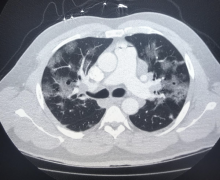

November 11, 2020 — Low-dose computed tomography (CT) screening methods may prevent one death per 250 at-risk adults screened, according to a meta-analysis of eight randomized controlled clinical trials of lung cancer screening.